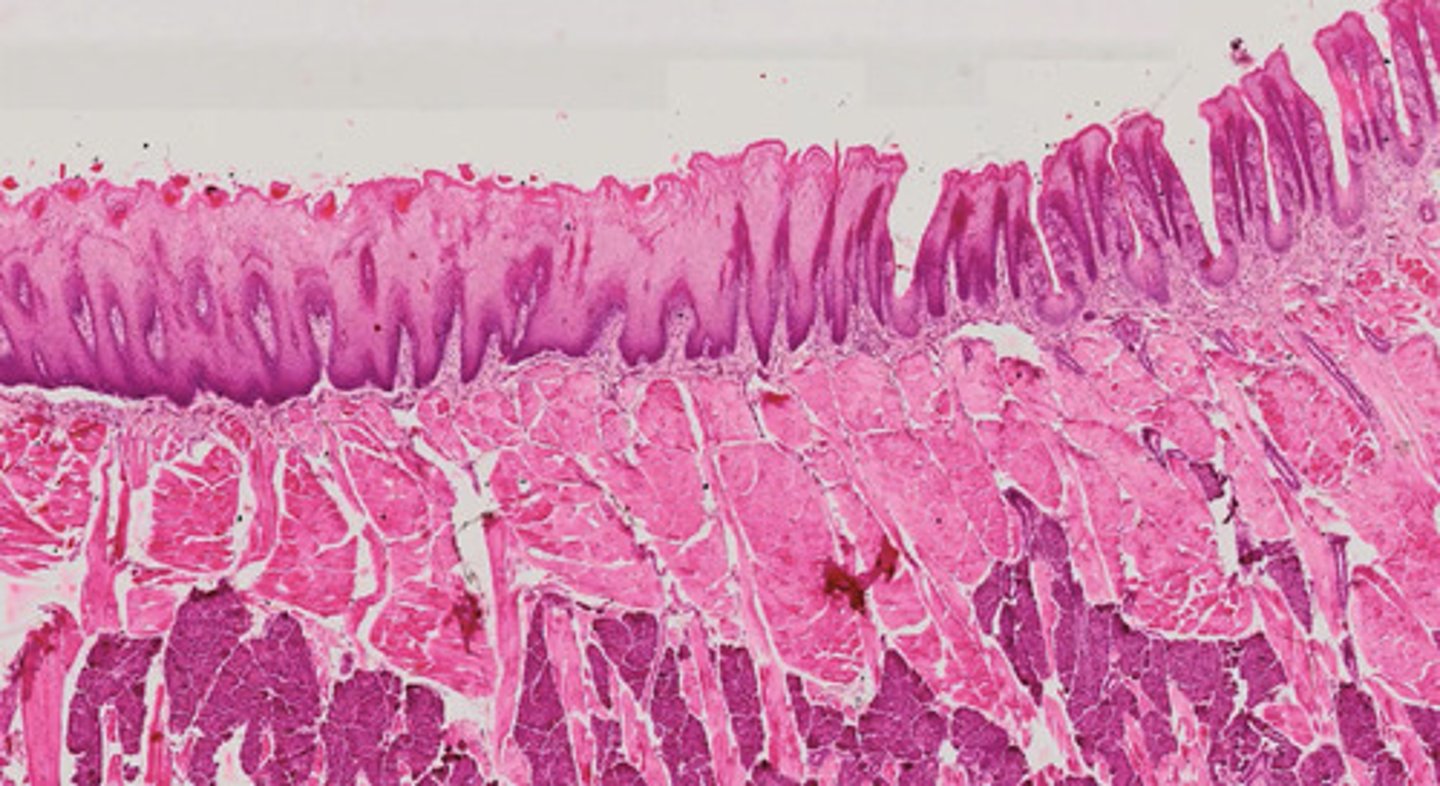

Język-brodawki liściaste i nitkowate (H+E)

Język-brodawki nitkowate i grzybowate (H+E)

Język-brodawki okolone (H+E)